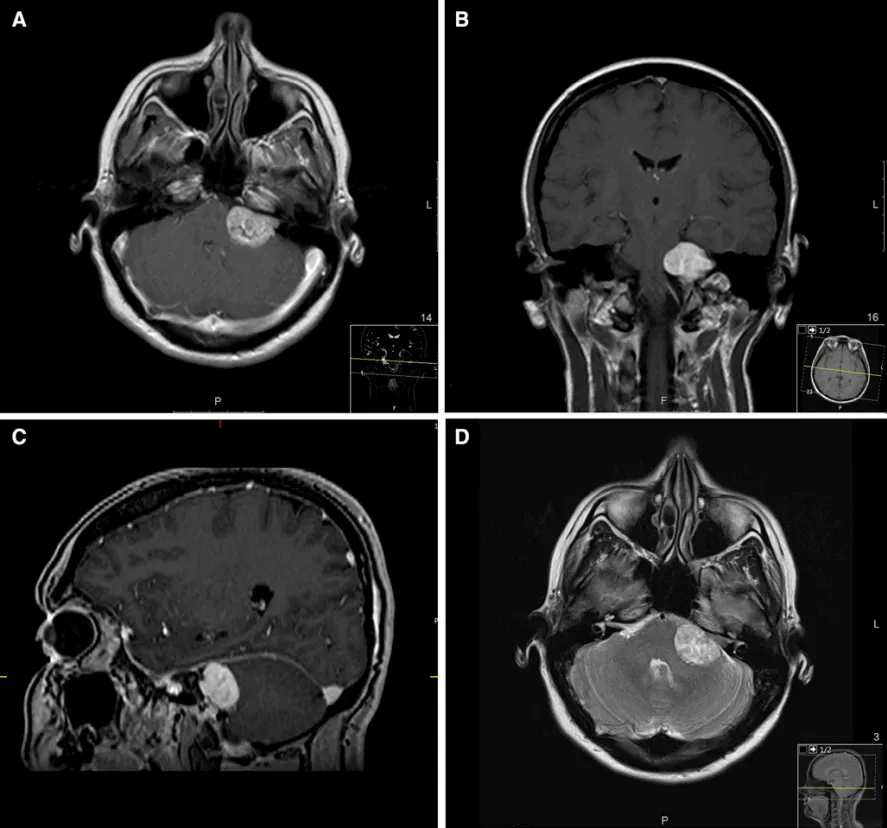

检查结果提示:左侧桥小脑角区存在31×27×23mm的听神经瘤。回顾病史发现,患者实际已有4年轻度双侧耳鸣史,因症状轻微未予重视。

该位于内听道区域的良性肿瘤,正是长期被误诊为普通偏头痛的夜间头痛的根本病因。